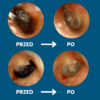

Koniec z ryzykiem urazów i infekcji — patyczki często powodują podrażnienia, infekcje i perforację błony bębenkowej. Pełna kontrola dzięki obrazowi HD 1080p — widzisz woskowinę i swobodnie ją usuwasz, zamiast ją wpychać.

Pełna kontrola dzięki obrazowi HD 1080p — widzisz woskowinę i swobodnie ją usuwasz, zamiast ją wpychać. Miękkie silikonowe końcówki zamiast patyczków — precyzyjnie usuwa woskowinę, bez ryzyka zarysowań i dyskomfortu

Miękkie silikonowe końcówki zamiast patyczków — precyzyjnie usuwa woskowinę, bez ryzyka zarysowań i dyskomfortu Higieniczne i oszczędne — wielorazowe końcówki redukują odpady i koszty wymiennych patyczków.

Higieniczne i oszczędne — wielorazowe końcówki redukują odpady i koszty wymiennych patyczków. Szybka ulga — natychmiastowy efekt komfortu i czystości uszu bez wizyt u specjalisty.

Szybka ulga — natychmiastowy efekt komfortu i czystości uszu bez wizyt u specjalisty.